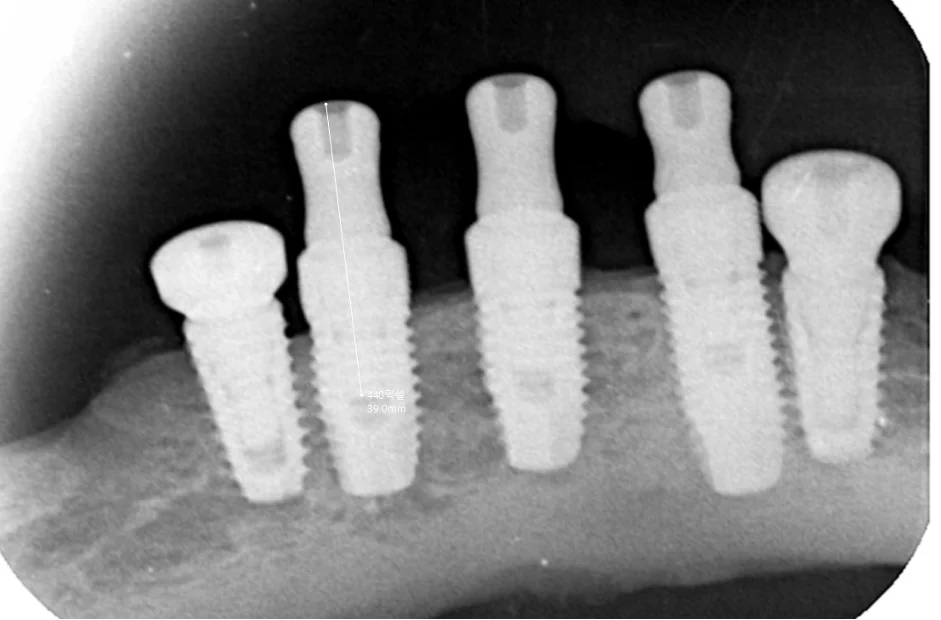

[📸 치료 중 임플란트 엑스레이] (촬영일: 2024년 10월)

1️⃣ 임플란트 추가 식립 및 조기 기능 회복

계획된 어금니 위치에 임플란트를 안전하게 추가 식립하고,

11일 뒤에 임시 보철물을 장착하여

빠르게 일상적인 씹는 기능을 회복시켜 드렸습니다.